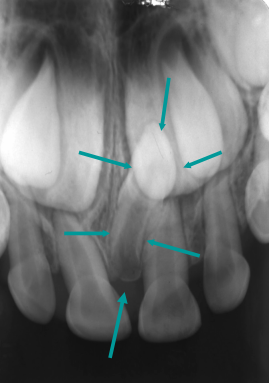

Define mesiodens

Supernumary tooth that develops on the maxillary midline

Describe the characteristics of mesiodens (6)

• Can prevent the eruption of central incisors

• Small tooth in a vertical, inverted or horizontal position

• Normal density of teeth

• Usually more palatal

• PDL space and lamina dura present

• Normal tooth architecture